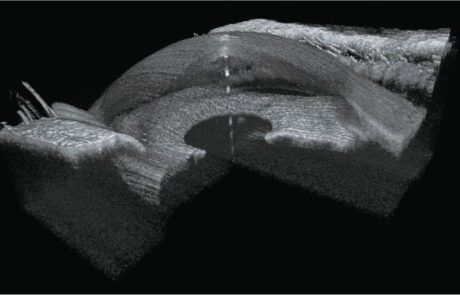

400KHz Ultra-Widefield

Full-Range SS-OCTA

Das TowardPi OCT-System ist das weltweit erste 400-kHz-Ultraweitwinkel-Vollbereichs-SS-OCTA mit vollständig eigenentwickelten Kernkomponenten.

Es ermöglicht eine 120°-Ultraweitwinkel Aufnahme in nur 7–15 Sekunden und liefert hochauflösende Bilddaten bei maximaler Effizienz.

Integrierte KI-Algorithmen unterstützen präzise Segmentierung, choroidale OCTA-Analysen sowie umfassende Fluss- und Strukturmessungen. Exklusive Funktionen wie OCTA des vorderen Augenabschnitts, iSpot-Analyse und Gefäßdichtebewertung eröffnen neue diagnostische Möglichkeiten im modernen Krankheitsmanagement.

Klinische Bilder